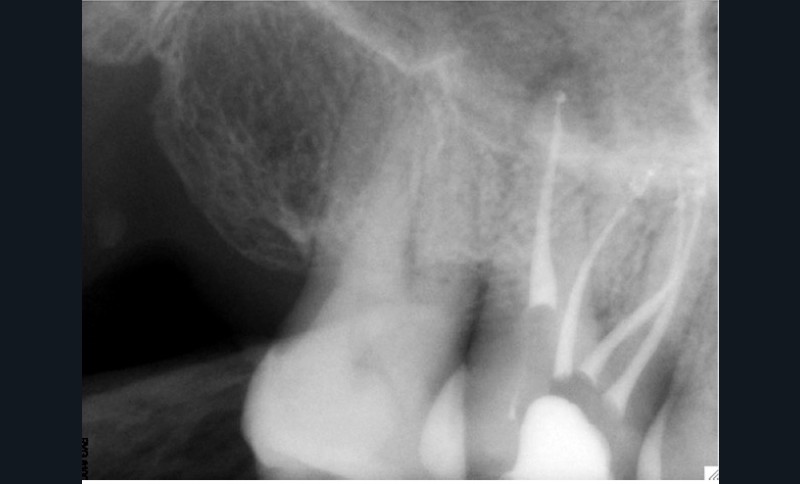

L’utilisation du scanner, et maintenant du CBCT, bouleverse l’idée très radiographique que nous avions du système canalaire.

En effet, la culture endodontique, fondée sur les critères radiographiques, a fait oublier les études de Hess et Zurcher (1925) qui mettent en évidence la complexité du système endo-canalaire [1]. Ce système présente une cavité principale (par exemple, le canal principal) ainsi que des canaux accessoires/latéraux. 25 % de ces microcanaux peuvent être interconnectés les uns aux autres, avec une densité plus importante de ramifications dans la région apicale du canal principal [2].

Rebondissant sur l’imagerie 3D et la mise en évidence des anatomies canalaires complexes, Peters, en 2001, décrit l’insuffisance instrumentale dans le traitement endodontique, et montre que 35 % des surfaces sont intactes après préparation canalaire correctement menée [18].

Endal, en 2011, montrait également, en utilisant le micro CT Scanner, l’insuffisance de nettoyage des isthmes inter-canalaires à nos techniques conventionnelles [19]. L’utilisation du laser Er:YAG devenait alors incontournable dans le nettoyage de ces isthmes et des zones non instrumentées (fig. 2 et 3).

Si les isthmes sont particulièrement mis en évidence au niveau des molaires mandibulaires, cela devient médicalement important au niveau des molaires maxillaires.

La diffusion bactérienne et de leurs toxines, au niveau des molaires maxillaires est à l’origine d’un grand nombre de sinusites maxillaires chroniques, d’origine dentaire. Celles-ci sont principalement causées par l’absence de traitement du deuxième canal MV, qui existe dans 90 % des cas, et il est à noter que ces deux canaux – MV1 et MV2 – sont également reliés par un isthme.

Le nettoyage des isthmes intercanalaires reste un réel problème, et semble responsable de nombreux échecs [43]. Par ailleurs, il est nécessaire d’utiliser des instruments qui évitent de propulser les débris, tant apicalement que latéralement, en obturant les entrées isthmiques avec des débris compactés.

L’utilisation d’instruments en nickel titane, tels que le XP Shaper (FKG), le Vortex blue (Dentsply) ou le Profile (Dentsply), optimise la remontée des débris et s’inscrit dans cette nouvelle philosophie. En conséquence, la combinaison XP Shaper, XP Finisher et l’irrigation avec l’Er:YAG semblent optimiser nos traitements [44,45].

Le passage du laser est répété plusieurs fois, en début, au milieu et en fin de préparation. Un protocole peut alors être proposé : 40 mJ ; 20 Hz (fig. 7). L’utilisation de biocéramiques Bioroot (Septodont) ou Total Fill R (FKG) permet de sceller le système ainsi nettoyé, en assurant une action biologique de longue durée [46] (fig. 8a à c).